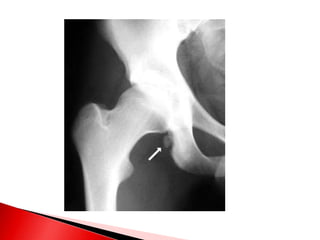

 Induce una actividad osteoclasica extrema en

los huesos con la consiguiente elevación de

calcio iónico en LEC

 La actividad osteoclasica del hueso supera

pronto al deposito de osteoblastico supera

 Razón de consulta fractura ósea

 La actividadosteoclasica del hueso supera pronto al deposito de osteoblastico supera pronto al deposito.  Siendo que uno leve se compensa  Razón de consulta fractura ósea